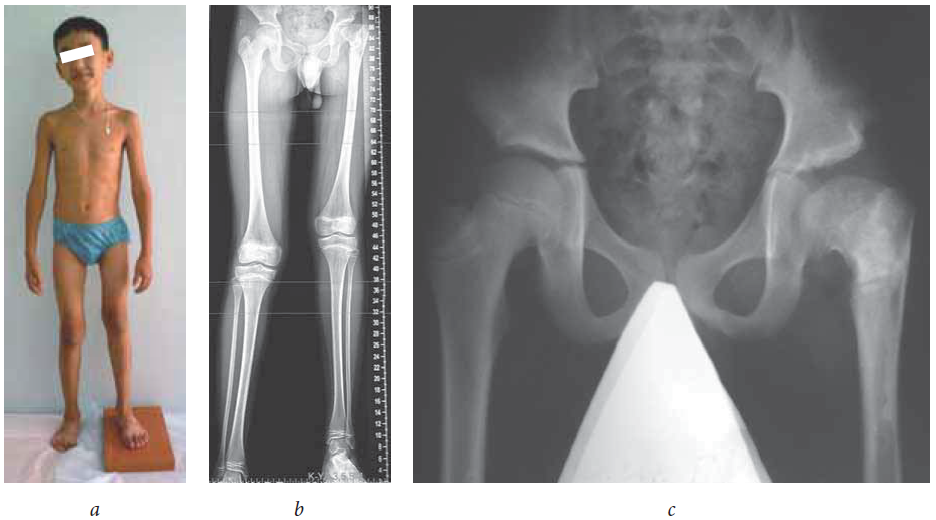

Проведено обследование 15 детей в возрасте от 6 до 16 лет (средний возраст — 11,5 ± 0,72) с последствиями острого гематогенного остеомиелита (ПОГО) проксимального отдела бедра и укорочением пораженной нижней конечности на величину от 1,0 до 6,0 см (рис. 1). Средняя величина укорочения пораженной нижней конечности составила 3,8 ± 0,53 см. При этом имела место гипоплазия стопы на стороне поражения, и ее укорочение по сравнению с контралатеральной стопой составило в среднем 2,7 ± 0,58 % (рис. 2, а).

Рис. 1. Пациент Д., 10 лет, с последствиями острого гематогенного остеомиелита проксимального отдела левого бедра: а — фото больного (укорочение левой нижней конечности 3 см); б — панорамная рентгенограмма нижних конечностей; в — рентгенограмма тазобедренных суставов